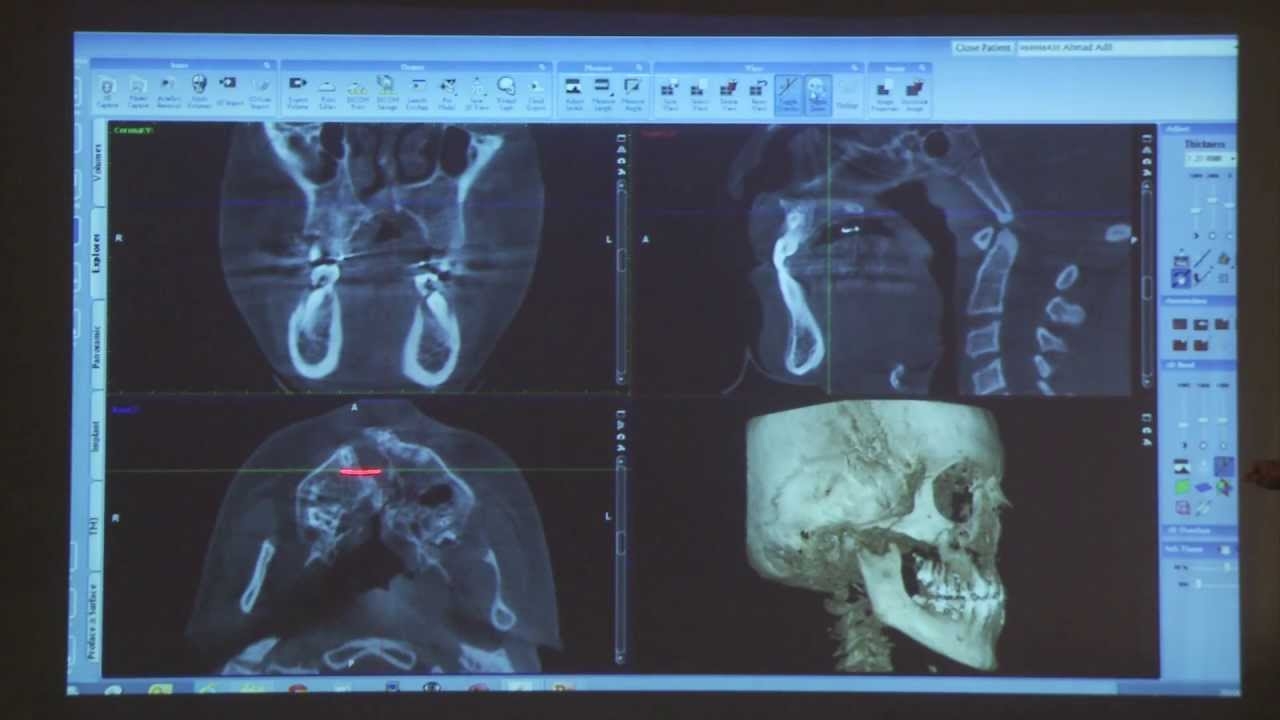

Clinical CBCT cases Prof Max Heiland